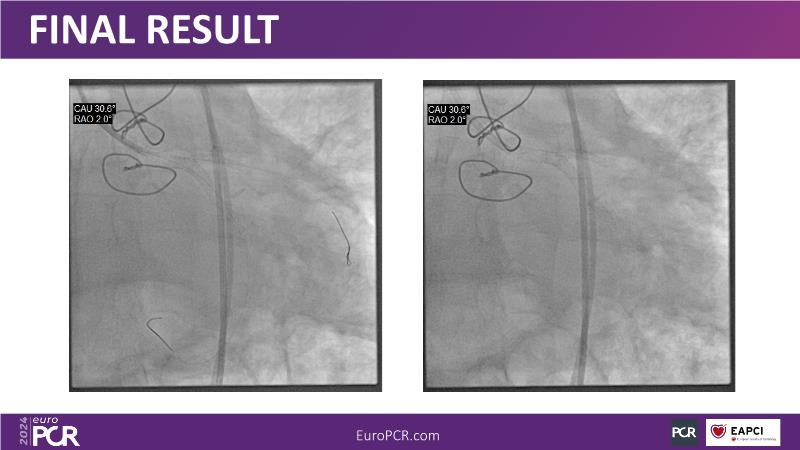

Sirolimus-coated balloon: expanding the scope of indications for complex coronary artery disease treatment

Watch this session to gain case-based insights on using DCBs in complex settings. Learn valuable tips and tricks for optimal DCB application, including the best timing and situations for their use. Discover how to effectively implement a hybrid strategy that combines DES and DCB when needed.

- To get a case based experience on how to use a DCB in complex settings